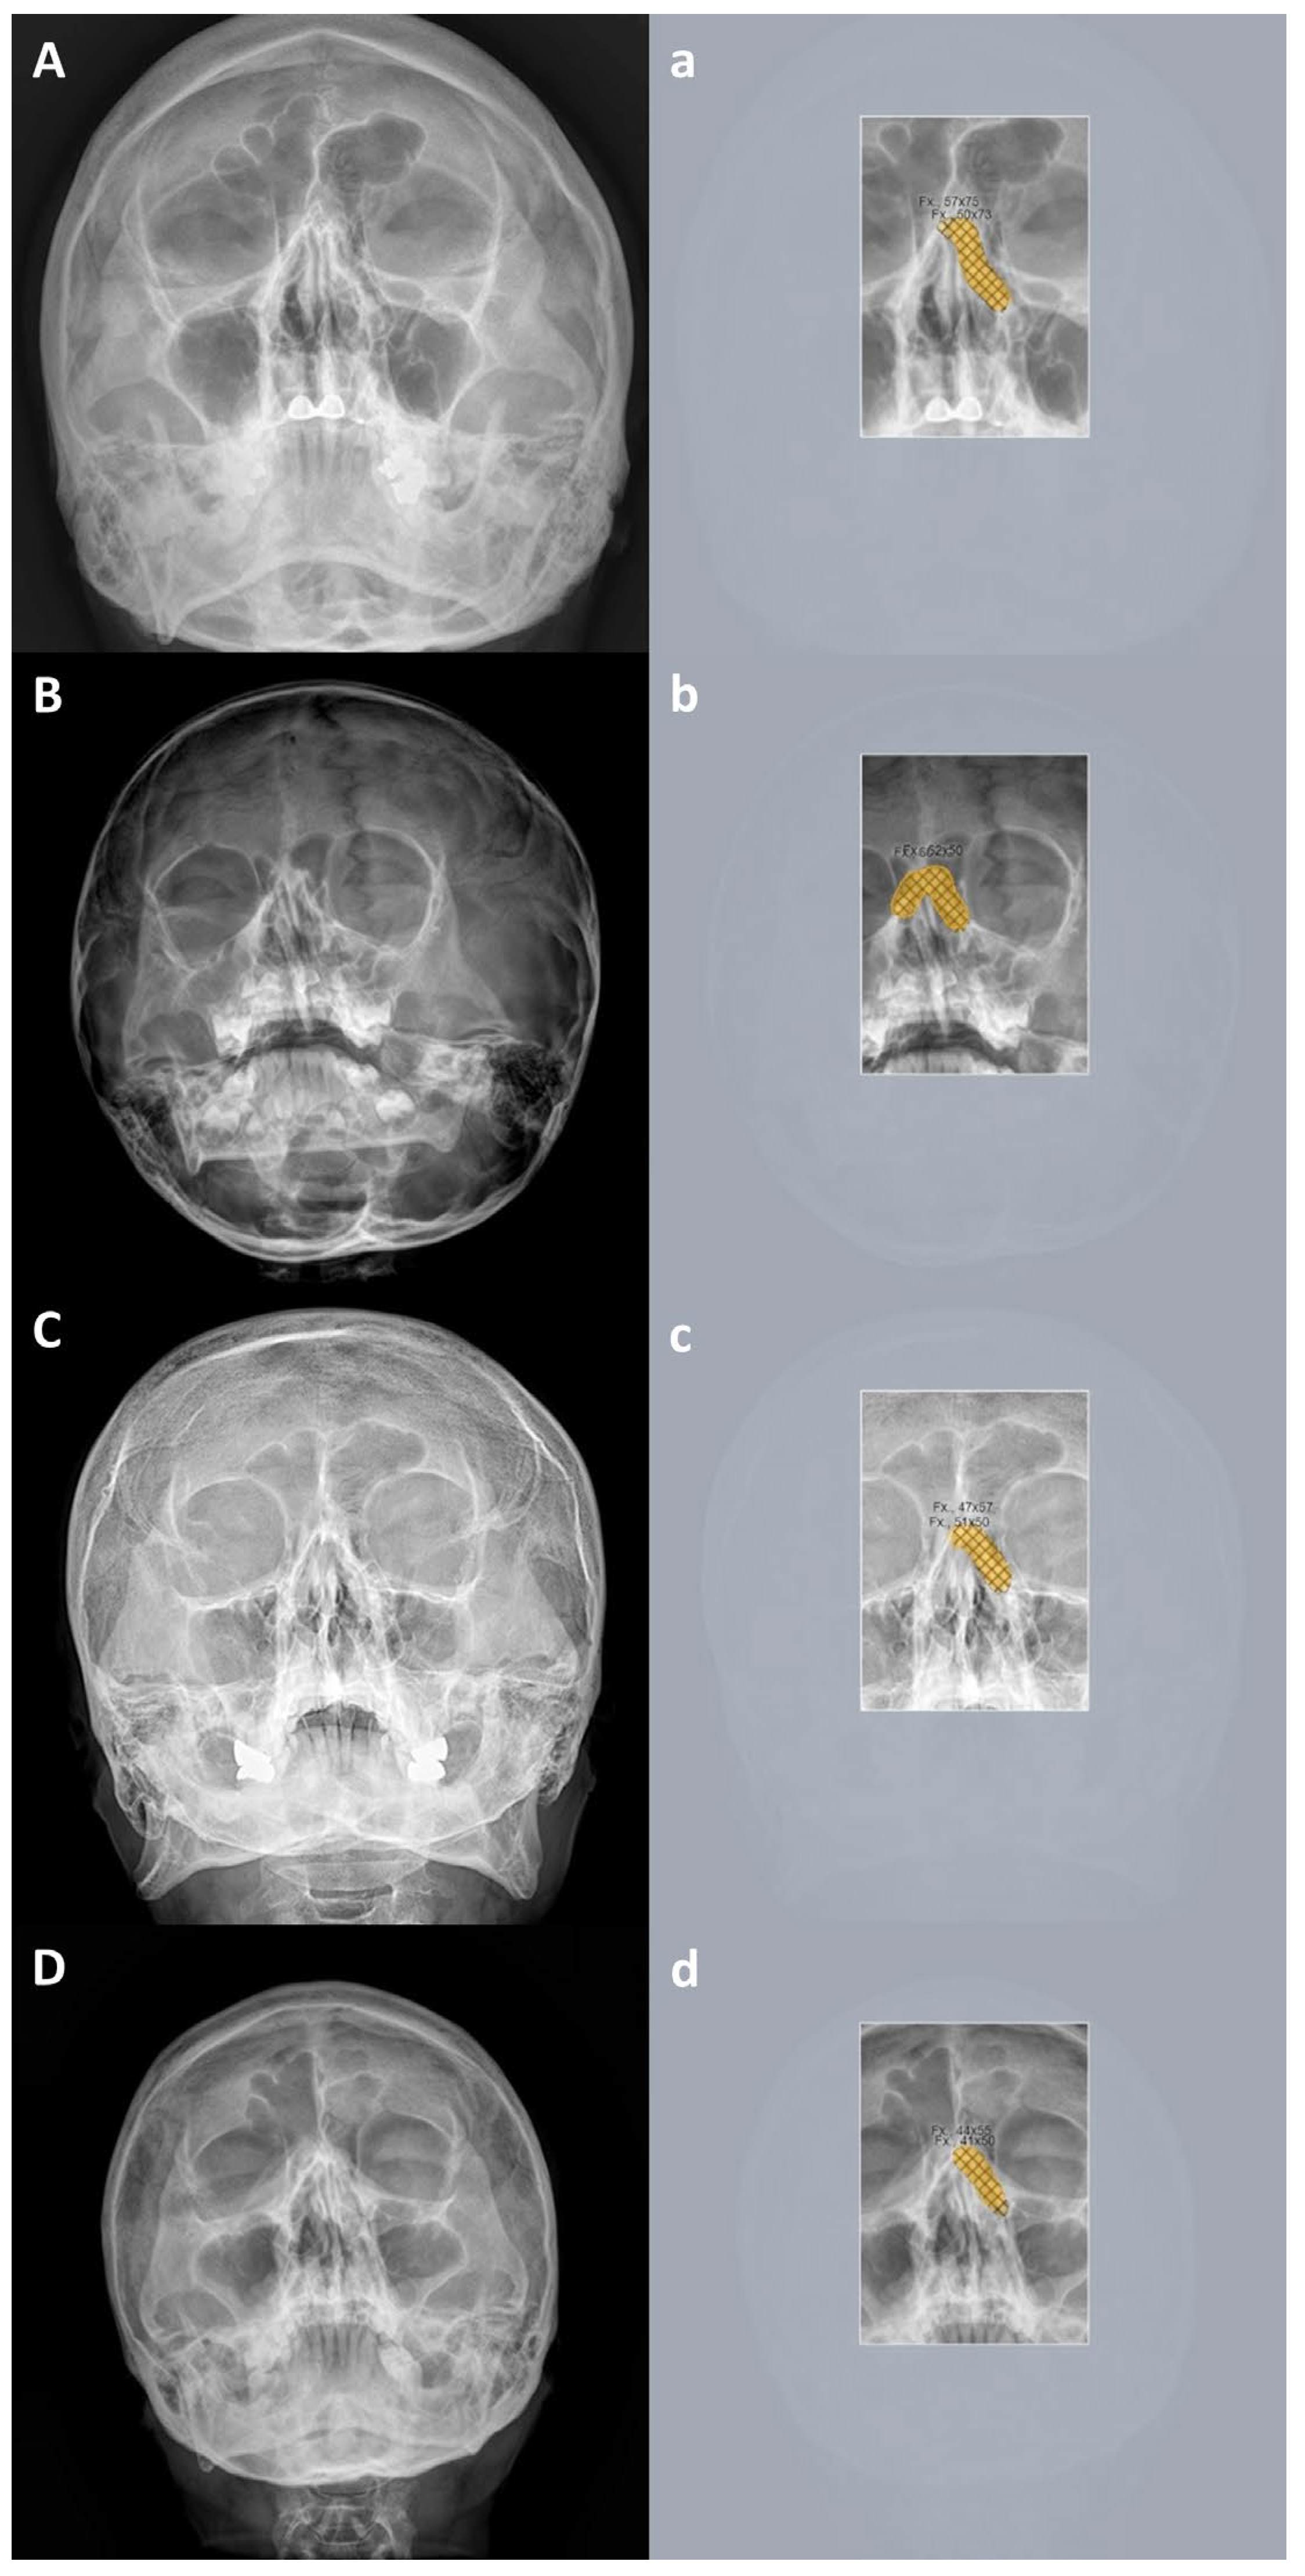

3.3. True Positive and False Positive of Deep Learning Models